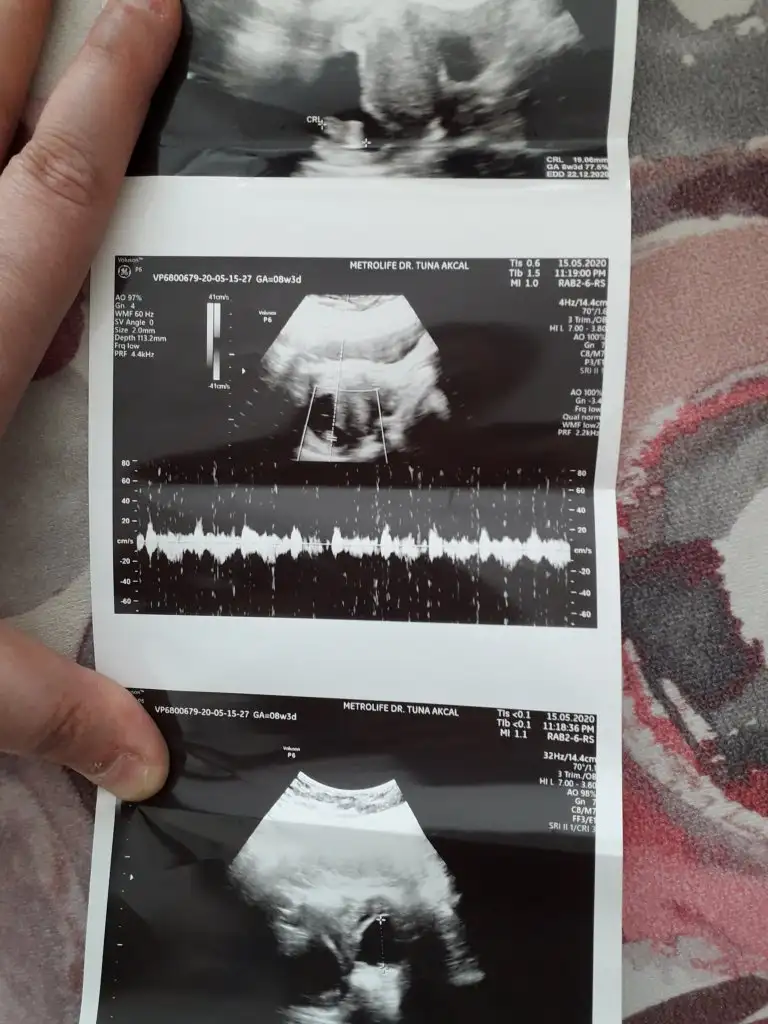

12. Haftada tahmin eden çok olmuyor. Benimki bi tahminde bulundu ama 16. Haftada netleşecek.Doktor bir tahminde bulunmuyor mu?

Doktorda kız dedi zaten 11+5 de gıttım buna daha yeni canım :) obur ay gıderım bide. Teşekkür ederim tatlımKız sanki emin olmadım çok net değil usg varsa 11 yada 13 hafta usg olursa paylaşın